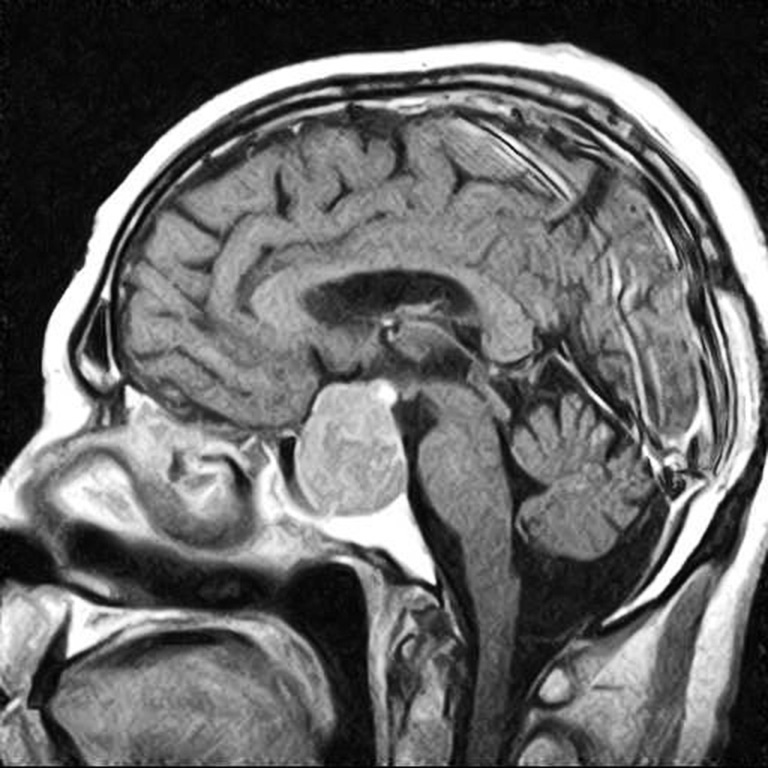

Fig. 3. Patient B., 58 years old, HIPA with retrosellar extension, anterior chiasmal position. Brain MRI: A – sagittal projection; B – coronal projection

A B

Fig. 4. Patient M., 54 years old, HIPA with antesellar extension, posterior chiasmal position. Brain MRI: A – sagittal projection; B – coronal projection